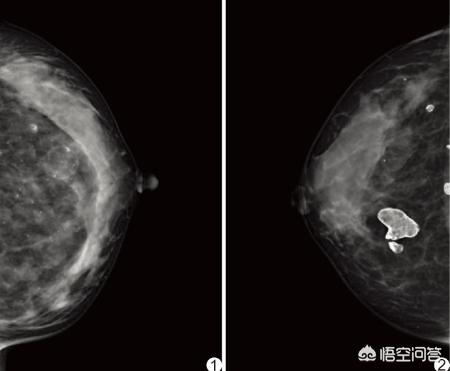

无创,无排异,形态自然,存活下来后永久有效这是它最大的优点。缺点是不成活的脂肪细胞容易液化,纤维钙化,形成结节。这样的结节再外科诊断过程中很难与乳腺癌区分鉴别。所以要明确脂肪坏死和乳腺癌的区别。以减少误诊或不必要的手术。